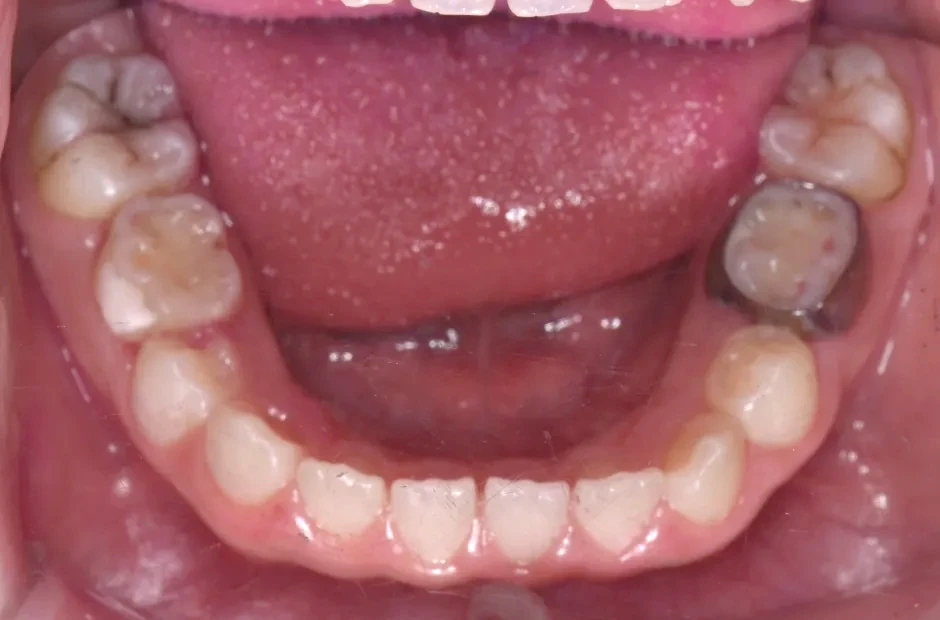

叢生

| 診断名・主訴 | 叢生 |

|---|---|

| 年齢・性別 | 10歳・女性 |

| 治療期間・回数 | 2年半 |

| 治療に用いた主な装置 | 拡大床装置 |

| 抜歯部位 | なし |

| 治療費 | 30万円(税抜) |

| リスク・副作用 | 装置による違和感・疼痛・歯肉退縮・歯根吸収・虫歯のリスクなど |

治療前

治療中

治療後